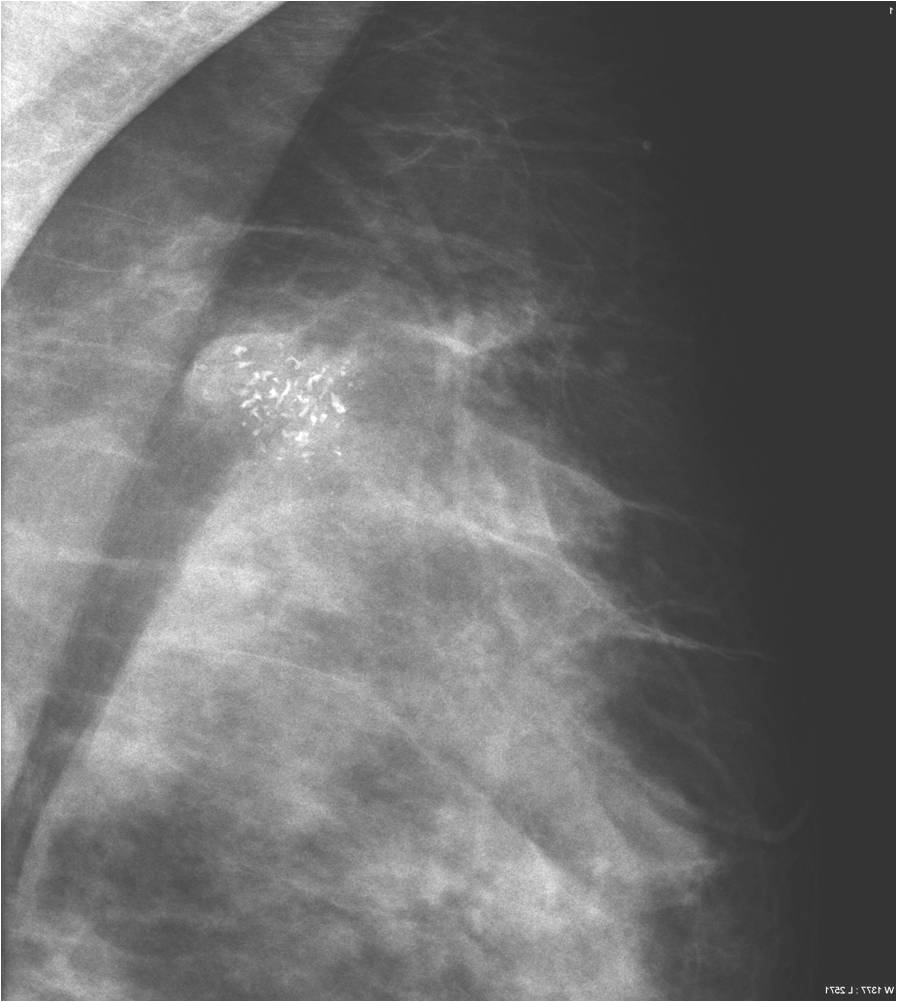

2. Digital mammography has displaced the analogue technic for today almost everywhere: (pictures 1,2,3) phosphorous plate or direct digital methods. For breast imaging the latter is the method of choice. Phases of image production separate. The image is produced on the detectors, but appears on the high resolution monitor and can be stored as a digital data set at various storage mediums (e.g.: CD, hard disk drives).

Image

Picture 1.

Picture 2.

Picture 3.

Advantages:

• significantly decreases radiation

• higher contrast and sharpness

• stable image quality

• depicts microcalcifications better than the analogue techniques

• no need for picture development, dark room

• eco friendly

• larger capacity

• image postprocessing possibilities (magnification, image inversion, contrast effects)

• teleradiology, telereporting

• supervisory function

• easier patient follow up, unnecessary exam or biopsy repetitions can be avoided

• simplified archiving

• CAD computer assisted diagnostic (recognition)

The spatial resolution of the digital technique is not higher than that of the analogue one!